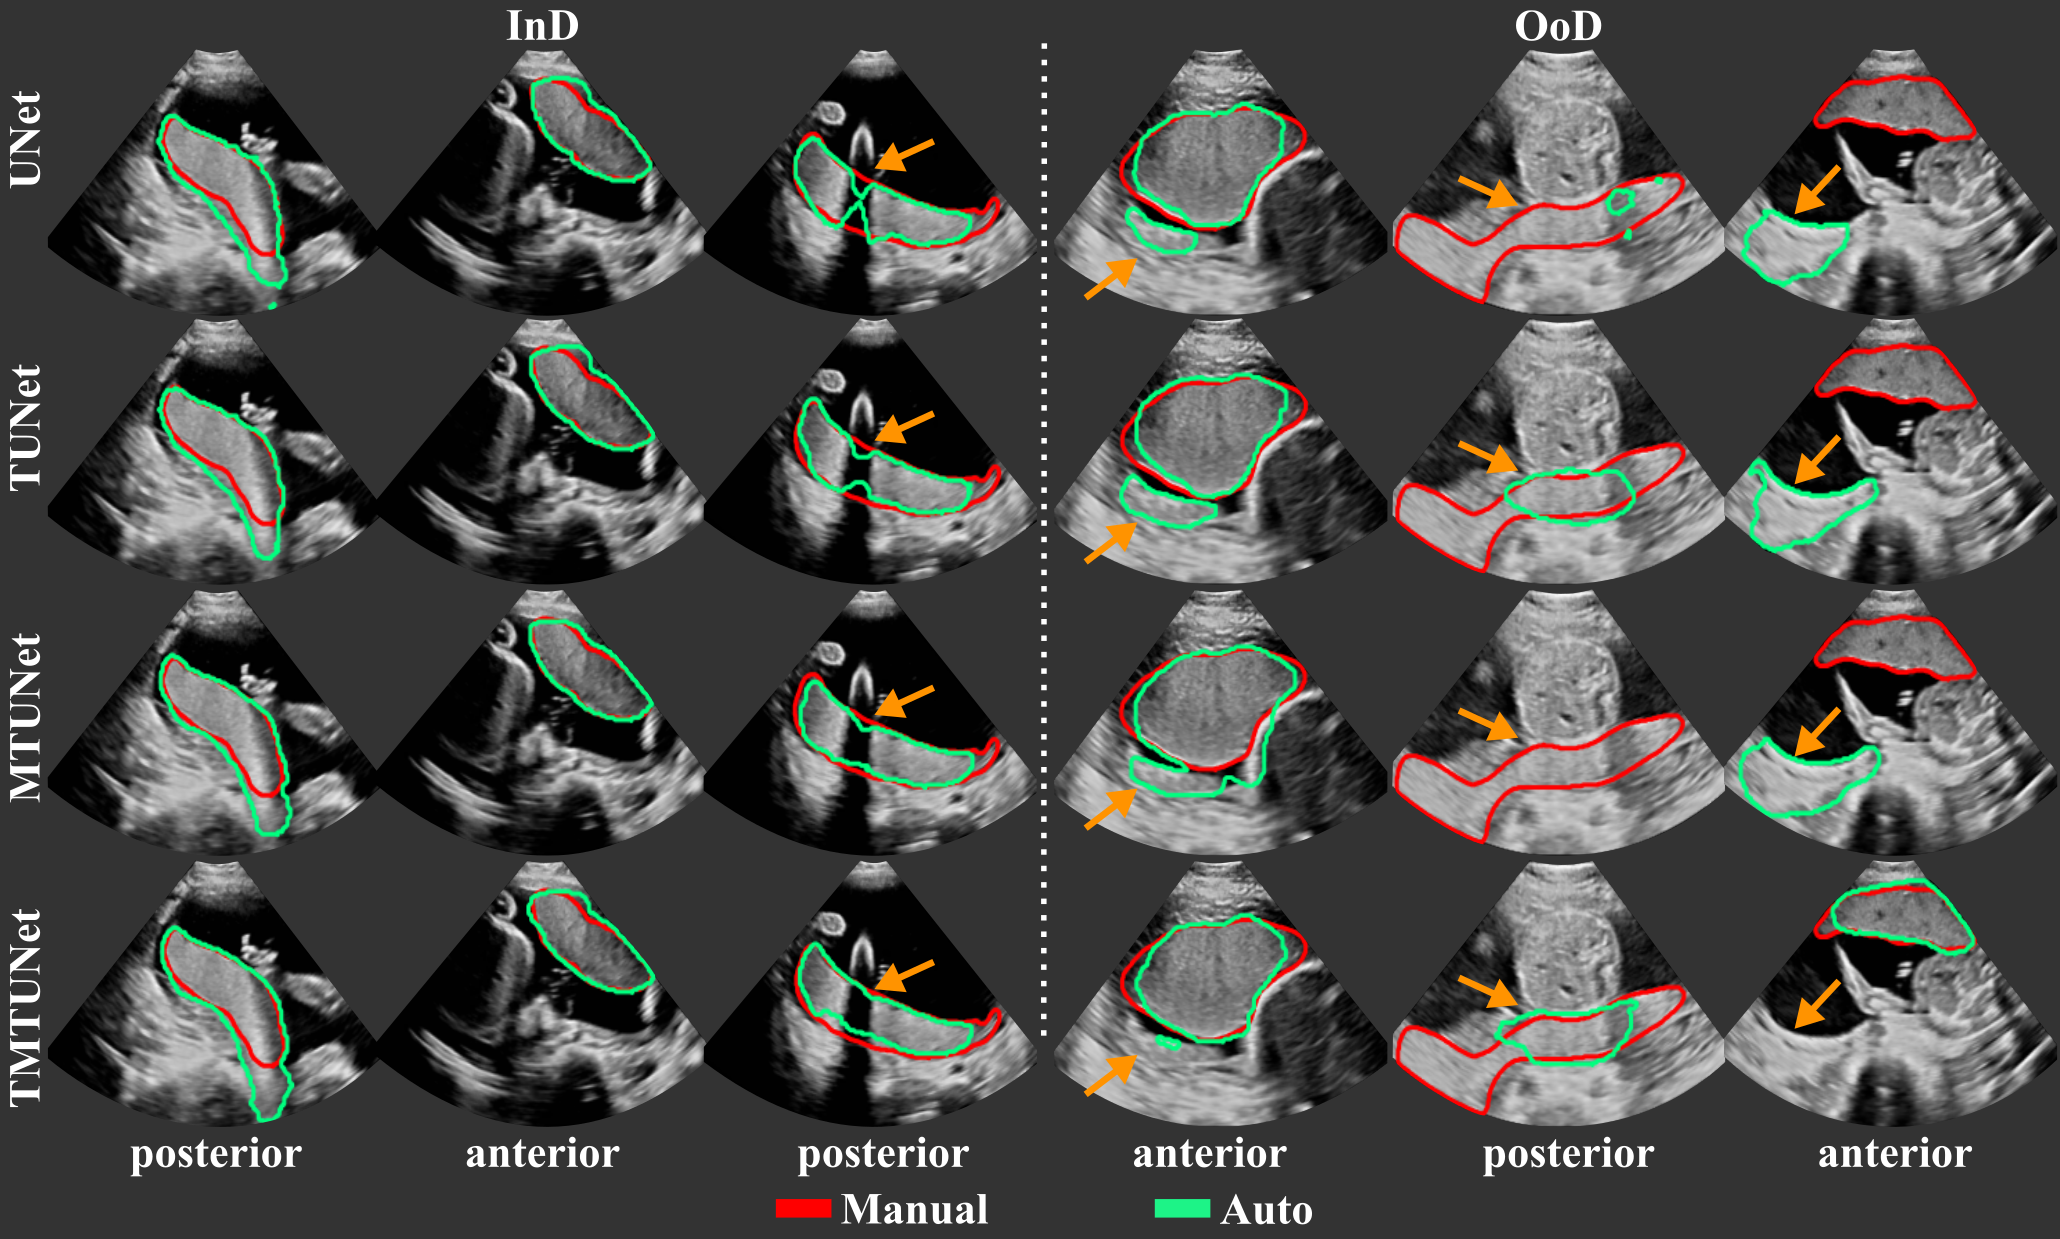

The segmentation performance of the different models measured by Dice, IoU, ASD and RHD are reported in Table 2 and representative segmentations comparing InD and OoD examples are shown in Fig. 4 with further examples in Fig. 11. Results using different training and validation sets suggest that anterior and posterior placentas represent two different distributions in the data. The baseline UNet trained on set A (only anterior) achieves a high Dice score of for the InD test set (anterior), but performs poorly on the OoD set (posterior) with a Dice score of . When trained on set P (only posterior), the Dice score for the InD set (posterior) is , and for the OoD set (anterior). The performance on the OoD sets is reduced with a higher standard deviation, indicating that the sets A and P alone are not representative enough for the segmentation of all types of placenta. These results confirm also that it is easier to segment anterior placentas, which achieve both a higher InD and OoD Dice score. The same trend is observed for the other performance metrics (IoU, ASD, RHD) and models (TUNet, MTUNet, TMTUNet).

Figure 4 visualizes examples comparing the segmentation when the images was InD or OoD data. Multi-task models, especially TMTUNet (row 4) show a more robust performance with respect to OoD data. For example, UNet tries to segment a posterior placenta in OoD of example 2 and an anterior placenta in OoD of example 3. Also, MTUNet and TMTUNet are more robust to image artifacts, such as shadows, which is shown in InD of example 3. Further examples can be found in Fig. 11 in the appendix.